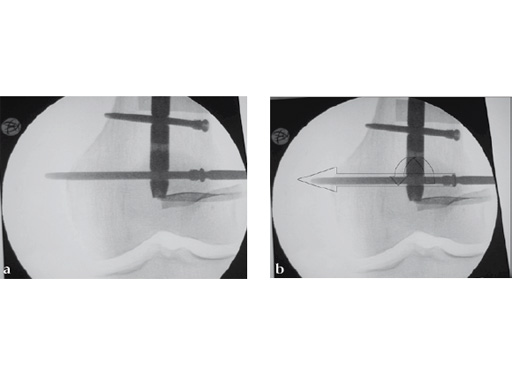

Drilling does not have to be very precise as the ASLS tolerates deviance. An exact amount cannot be given but up to 15 seems to be unproblematic (Fig 4).

The screw-sleeve construct is pushed into the nail's locking hole by hand. For the final placement, a light hammer (100 gr) may be used (Fig 8). You can actually feel and even hear the correct positioning. Use of a heavier hammer may lead to too deep placement or even pushing the sleeve too far through the locking hole. Control by image intensifier of the reamer and/or screw placement is only needed in the very early part of the learning curve (Fig 9).